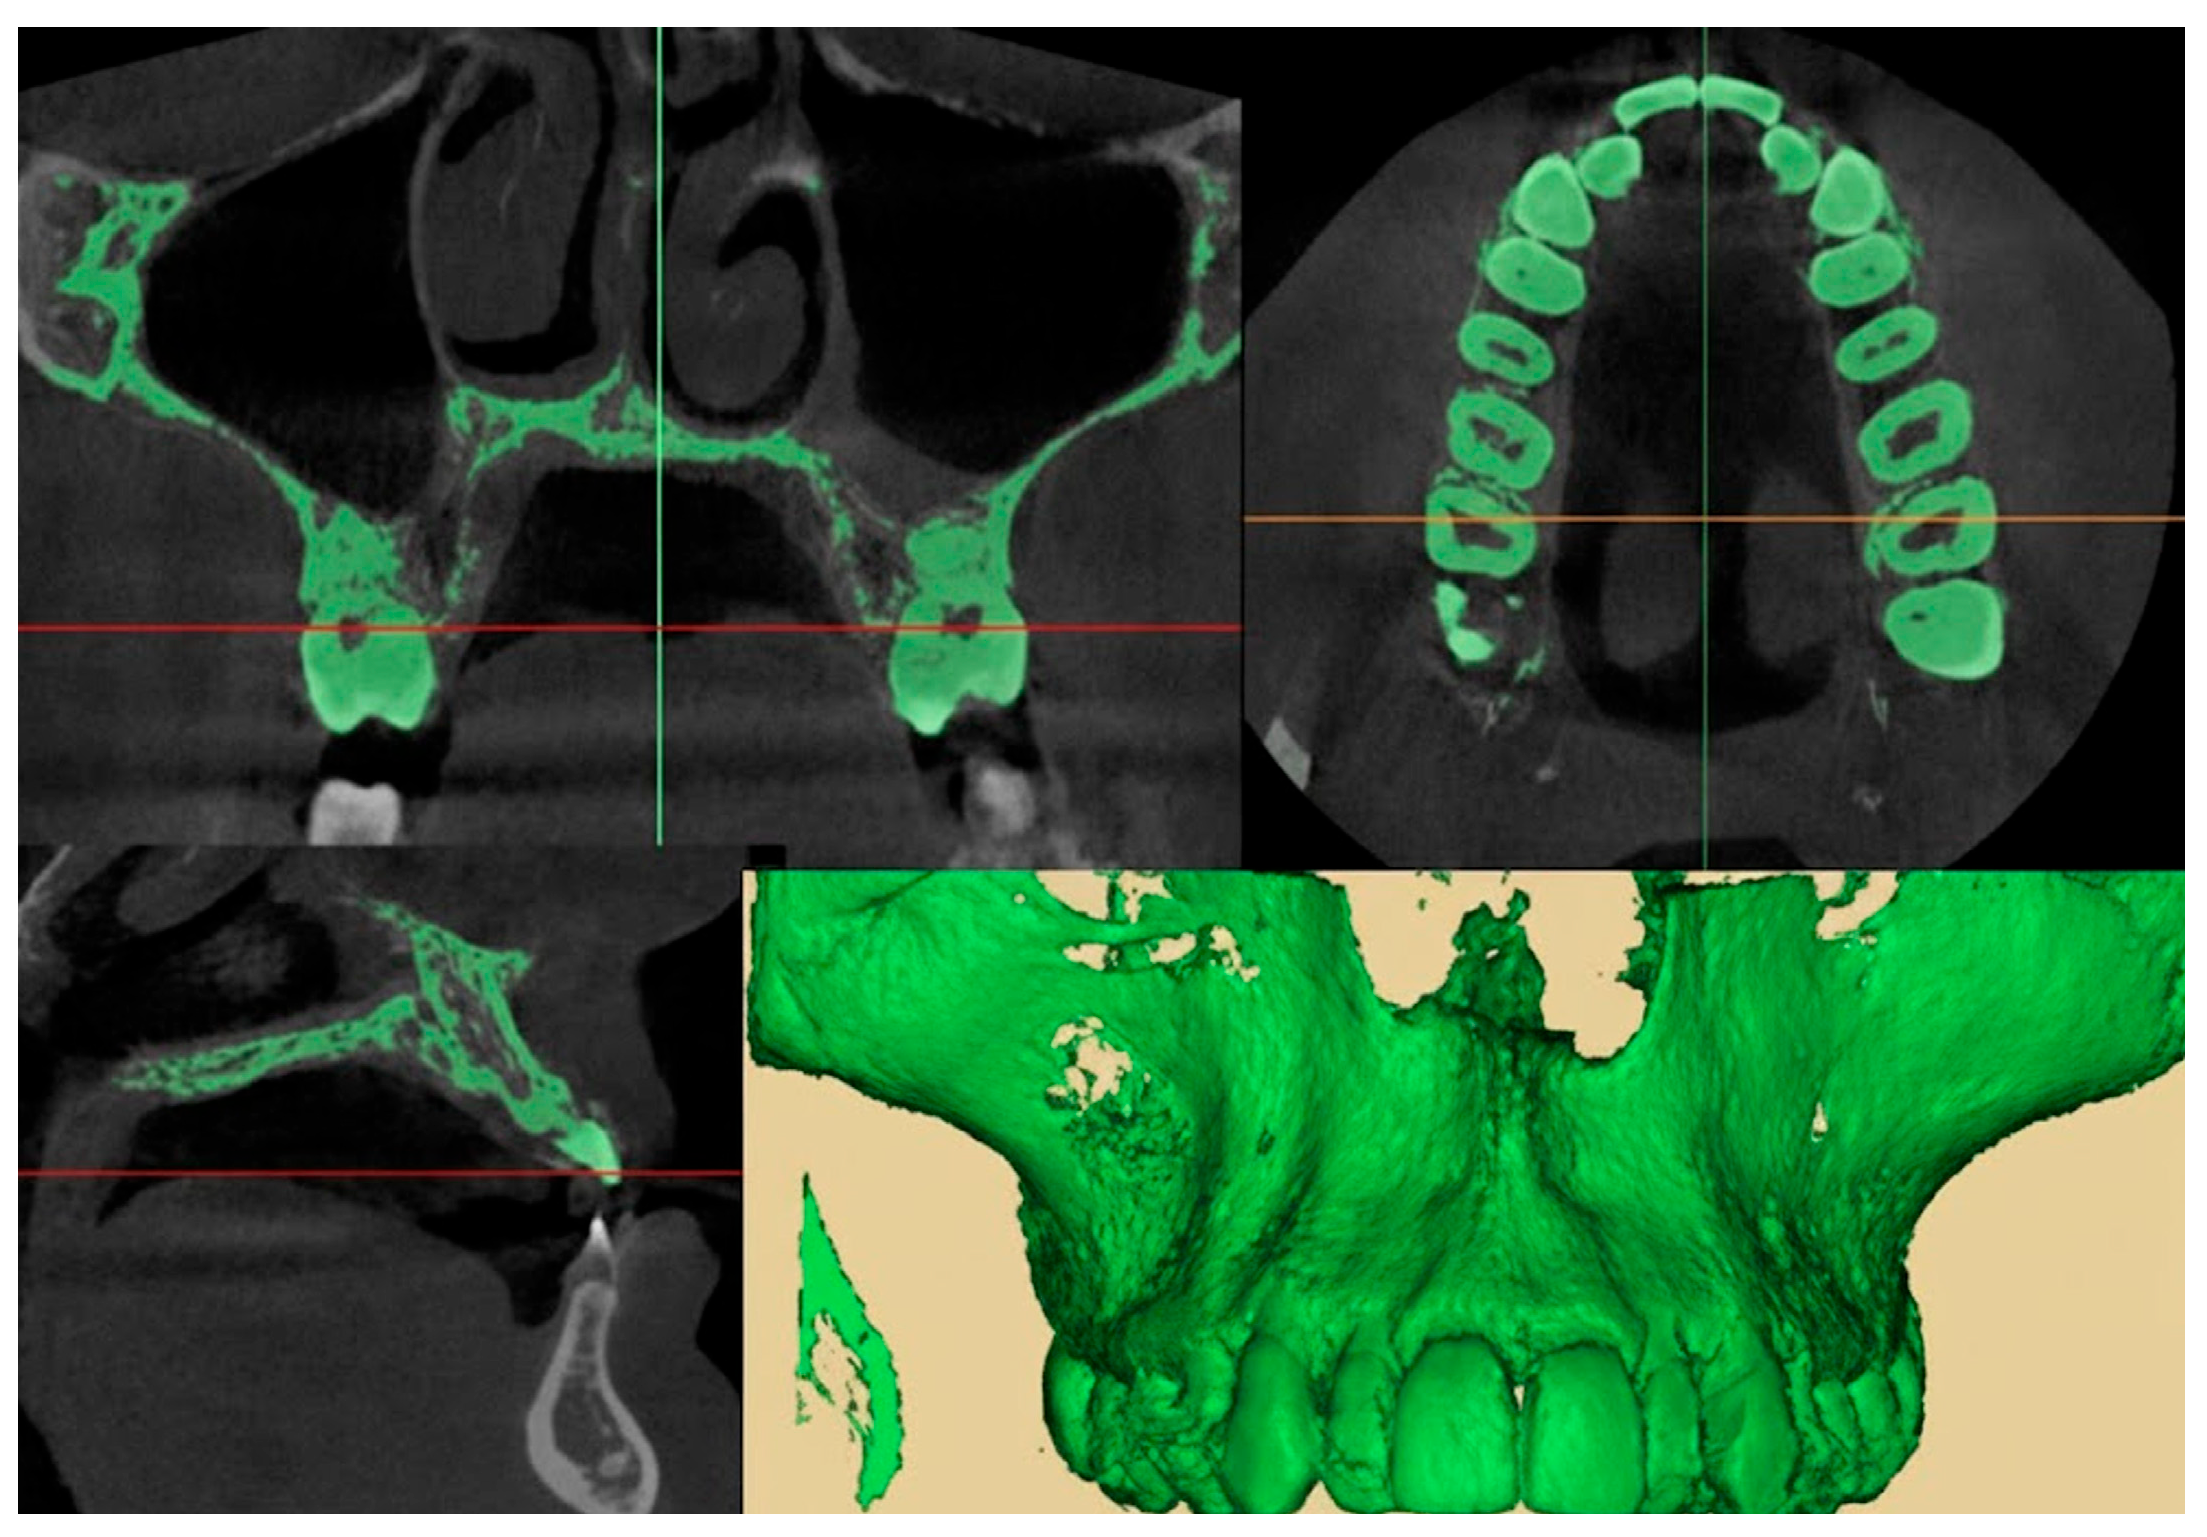

2.9.1. Qualitative Evaluation of Maxillary Expansion on Cone Beam Computed Tomography

3.2. Qualitative Evaluation of Maxillary Expansion on Cone Beam Computed Tomography